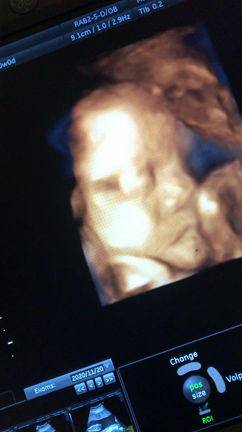

33w1d

2020年12月26日